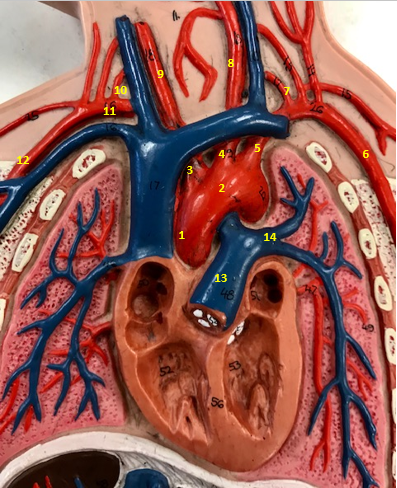

Aorta

Name #2

Brings blood out of left ventricle

Function of aorta

Brachiocephalic artery

Name #3

Supplies oxygenated blood to right arm shoulder neck and head

Function of brachiocephalic artery

Left common carotid artery

Name #4

Supplies oxygenated blood to left neck and head

Function of left common carotid artery

Left subclavian artery

Name #5

Supplies oxygenated blood to left arm shoulder

Function of left subclavian artery

Left axillery artery

Name #6

supplies blood to left armpit and upper limb

Function left axillary artery (6)

Left vertebral artery

Name #7

Supplies blood to brain and spinal cord

Function of left vertebral artery (7)

Left common carotid artery

Name #8

Supplies blood to left neck and head

Function of left common carotid artery (8)

Right common carotid artery

Name #9

Supplies oxygenated blood to right neck and head

Function of right common carotid artery (9)

Right vertebral artery

Name #10

Supplies blood to brain and spinal cord

Function of right vertebral artery (10)

Right subclavian artery

Name #11

Supplies blood to right arm and shoulder

Function of right subclavian artery

Right axillery artery

Name #12

Supplies blood to right armpit and upper limb

Function of right axillery artery (12)

Pulmonary trunk

Name #13

Bring blood out of right ventricle to lungs

Function of pulmonary trunk (13)

Left pulmonary artery

Name #14

Bring blood to left lung

Function of left pulmonary artery (14)